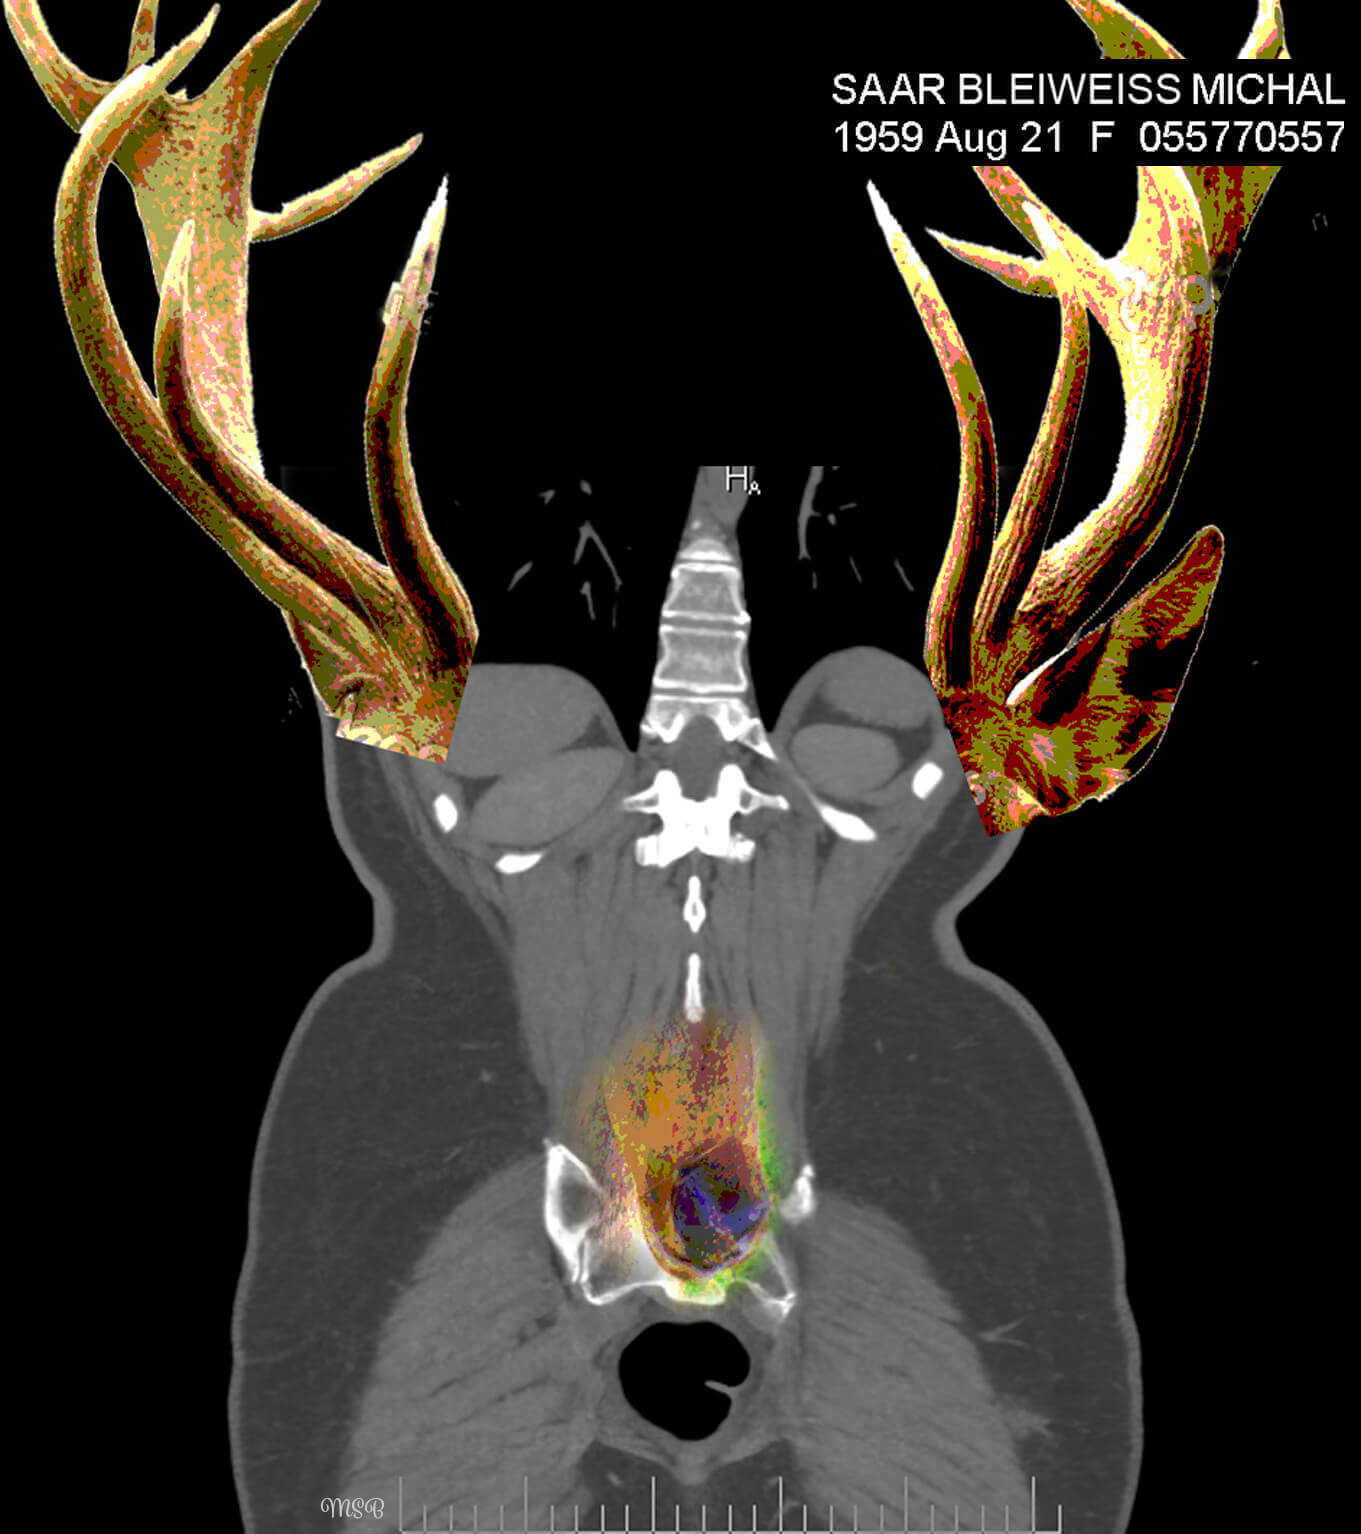

A reimagining of “self,” by Michal Saar-Bleiweiss

A few years ago, I became ill with Nephrostomy and had to undergo surgery. I was sitting with my husband, Mark, at a clinic in Ramat Aviv, Israel, in the office of a professor who specializes in CT* decoding. There, on two huge screens, for the first time I saw my body from the inside, and it was at this moment that my creative impulse arose.

The images before me were entirely in black and white, devoid of personality or character. There was no sign of the Michal that was me, and I felt a great desire and need to take these images to reinstate Michal, the person. When we returned home, I was curious about how I would feel when I looked at the images again—but this time on my computer screen. What I saw created an emotional storm within me.

This storm opened my “third eye,” enabling me to look inside myself. In my imagination I saw colors, dimensions, and expressive features, such as eyes. This was probably my way of internalizing my new reality, digesting what is going on inside me and brushing off my fears and pain. I wanted and needed to wake up each morning with a new smile and the ability to cope.

Having released the pain from the CT images, I found myself opening the next chapter in my imagination—creating digital collages.